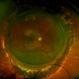

- A 23 year old female came with chief complaints of blurring of vision in left eye since 20 days. Fundus examination disc odema with choroidal granuloma.